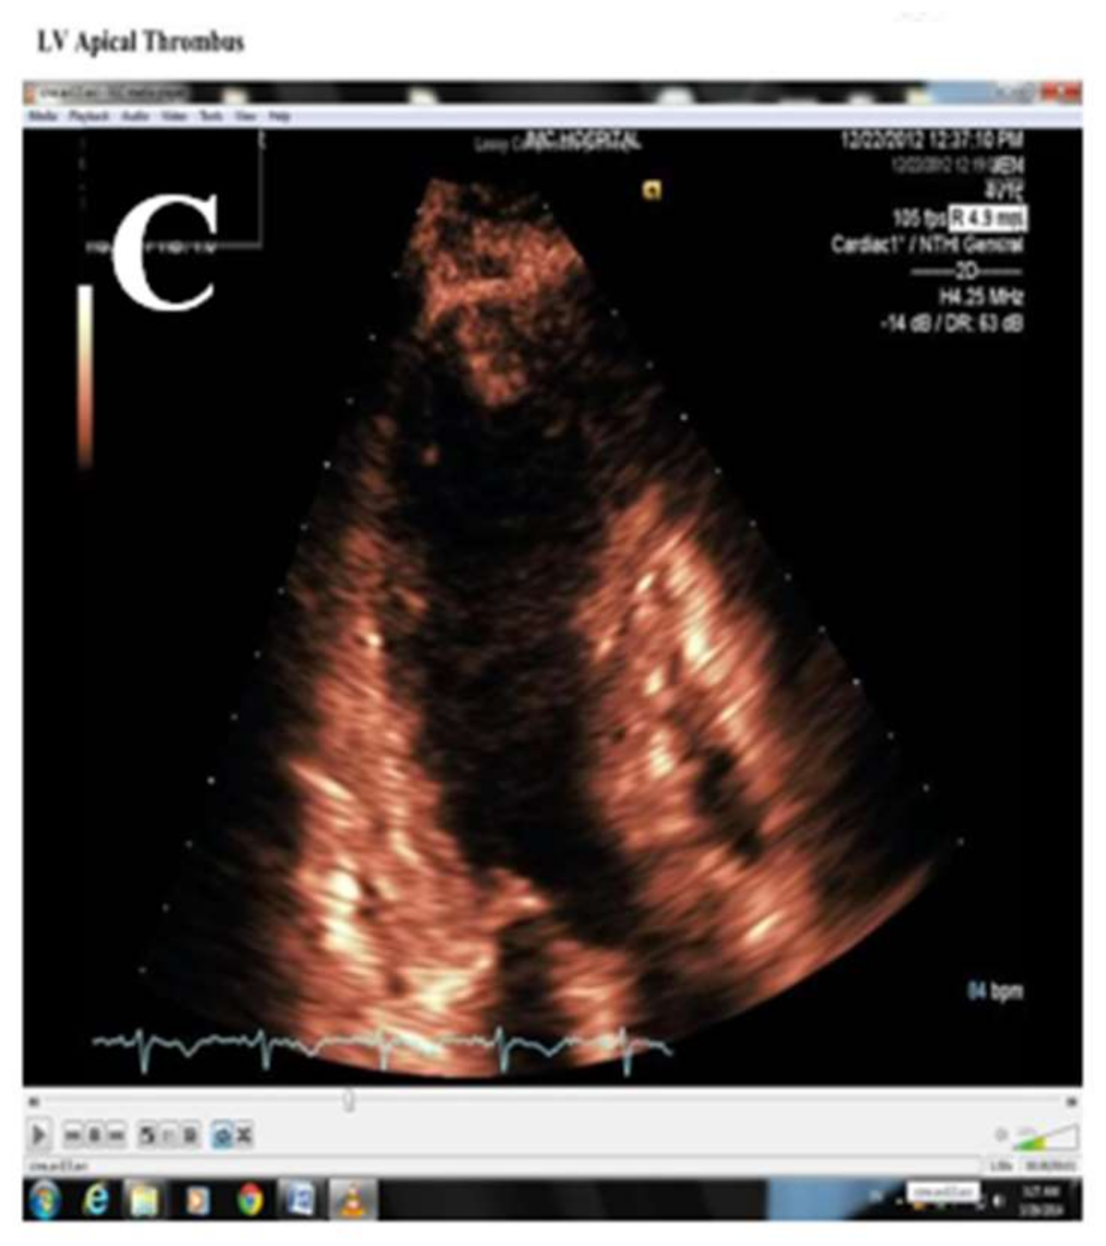

3.8. Thrombus and Prevention of Embolism in Patients with TTS

- Anabtawi, A.; Roldan, P.C.; Roldan, C.A. Takotsubo cardiomyopathy with a rapidly resolved left ventricular thrombus. J. Investig. Med. High Impact Case Rep. 2017, 5, 2324709617734238. [Google Scholar] [CrossRef] [Green Version]

- Herath, H.M.M.T.B.; Pahalagamage, S.P.; Lindsay, L.C.; Vinothan, S.; Withanawasam, S.; Senarathne, V.; Withana, M. Takotsubo cardiomyopathy complicated with apical thrombus formation on first day of the illness: A case report and literature review. BMC Cardiovasc. Disord. 2017, 17, 176. [Google Scholar] [CrossRef]

- Azzarelli, S.; Galassi, A.R.; Amico, F.; Giacoppo, M.; Argentino, V.; Giordano, G.; Fiscella, A. Apical thrombus in a patient with takotsubo cardiomyopathy. J. Cardiovasc. Med. 2008, 9, 831–833. [Google Scholar] [CrossRef] [PubMed]